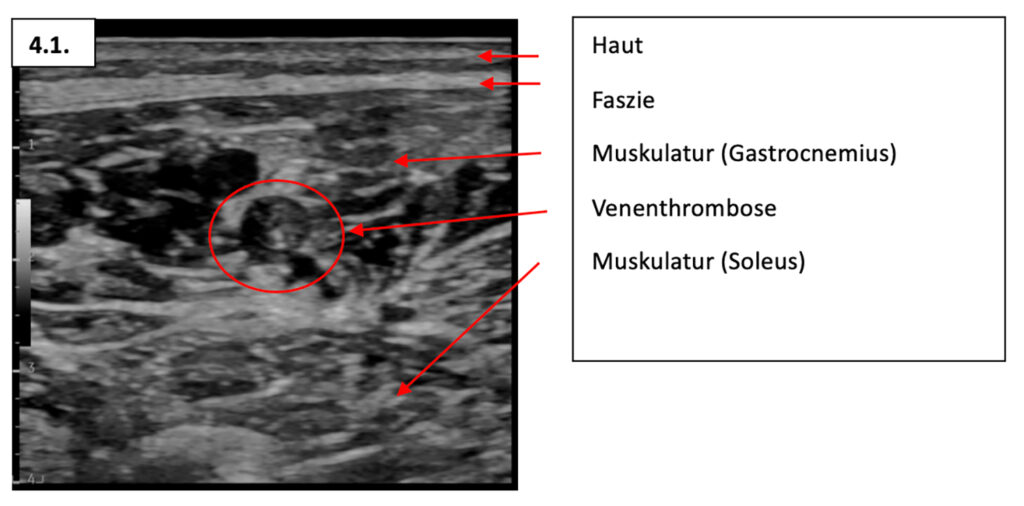

28-jähriger professioneller Fahrer mit distalem Abriss der Musculus semitendinosus Sehne links und druckdolenter Wadenmuskulatur. Begleitend findet sich duplexsonographisch eine langstreckige Muskelvenenthrombose im medialen Musculus gastrocnemius links (Thromboselänge 37cm – 57cm ab planta pedis) mit proximalem Endpunkt unmittelbar vor der Mündung in die Vena poplitea.

Wie im Rahmen des ersten Falles bereits angetönt ist die vermutete Dunkelziffer von oberflächlichen Venenthrombosen und Muskelvenenthrombosen wohl höher als die aktuelle Literatur vermuten lässt. Dies begründet sich insbesondere darin, dass man sich in der Literatur sowie in der duplexsonographischen Schnelldiagnostik primär auf die tiefen Beinvenenthrombosen fokussiert. Die Detektion von oberflächlichen Venenthrombosen und insbesondere Muskelvenenthrombosen ist deutlich schwieriger und bedarf einer gewissen Erfahrung. In einem Kollektiv von 18-35-jährigen Fußballspielern zeigt sich eine rund 10 x höhere Prävalenz von tiefen Beinvenenthrombosen als in der Allgemeinbevölkerung (Allgemeinbevölkerung: 1:10’000 vs. Fußballer 1.2:1000) [6]. Allerdings können nicht nur tiefe Beinvenenthrombosen nach kranial migrierten, sondern rund 10 % der Patienten mit einer oberflächlichen Beinvenenthrombose keine Progression ins tiefe Venensystem und im weiteren Verlauf eine Lungenembolie erleiden [7]. In Bezug auf die Beinvenenthrombosen in einem Kollektiv von Leistungssportlern ist somit nicht nur die Diagnostik herausfordernd, sondern auch die Therapie mittels oraler Antikoagulation. Dies aufgrund der Tatsache, dass sich eine Blutverdünnung nicht mit den Blutungsrisiken des Kontaktsports vereinbaren lässt. Das Antikoagulations-Management von kompetitiven Berufssportlern bedarf somit einer genauen Analyse des individuellen Blutungsrisikos, des sporttypischen Verletzungsrisikos, sowie der sononatomischen Begebenheiten der Thrombose. Im Sinne eines «informed consent» sowie einem «shared-decision-making» ist unter entsprechenden Vorsichtsmassnahmen mit Einbezug der Pharmakodynamik/-kinetik die Fortführung des Kontaktsports mit oraler Antikoagulation organisierbar.